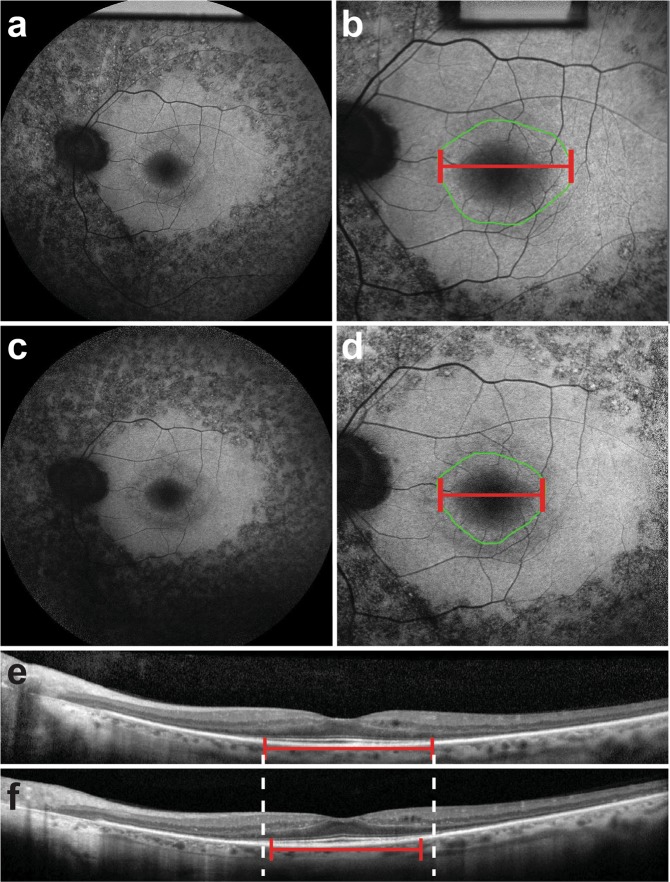

Figure 1.

Progressive changes in short-wave fundus autofluorescence imaging and spectral domain optical coherence tomography scans of a patient with RP1-autosomal dominant retinitis pigmentosa. Short-wave fundus autofluorescence (SW-FAF) images with a 55- (a) and 30-degree (b) field of view during the first clinic visit of a patient with autosomal dominant retinitis pigmentosa (adRP) caused by the RP1 gene. The corresponding spectral domain optical coherence tomography (SD-OCT) scan is also shown (e). On the SW-FAF images, the area of the hyperautofluorescent ring is outlined in green (9.2 mm2), whereas the horizontal diameter is indicated by the red line (3993 µm). On the SD-OCT scans, the ellipsoid zone (EZ) line width is also marked with a red line (2435 µm). On the follow-up visit 6 years later, the EZ line shortened to 2080 µm (f), while both the ring area and horizontal diameter on SW-FAF (d) also decreased to 5.8 mm2 and 2080 µm, respectively.